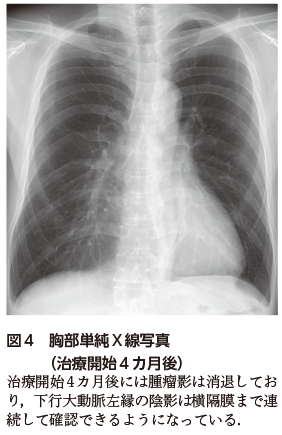

胸部単純X線写真では一見すると両肺野に明らかな異常陰影を指摘できないが,注意深く観察すると下行大動脈左縁の陰影が途切れていることがわかる(図1).このような所見をシルエットサインが陽性であると表現し,病変が下行大動脈と接していることを示している.このような心陰影と重なった結節影や腫瘤影を見つける際に,下行大動脈とのシルエットサインの有無はきわめて有用な所見である.胸部CTではS6からS10にかけて腫瘤を認め周囲に粒状影を伴っており(図2),また腫瘤に隣接する気管支の壁肥厚もみられる(図2).これらの画像所見から肺化膿症を含めた感染症が第一に疑われたものの,原発性肺がんを含めた他疾患との鑑別目的に気管支鏡検査を施行した.経気管支肺生検(transbronchial lung biopsy:TBLB)を行い,一般細菌および抗酸菌培養検査は陰性であったものの,組織診では膿瘍や炎症細胞浸潤のほかにグラム染色およびグロコット染色陽性となる桿菌を多数認め,肺放線菌症が疑われた(図3).本症例では経口ペニシリン系抗菌薬による内服治療を開始し,治療開始後約4カ月時点で胸部単純X線写真上の腫瘤影はほぼ消退した(図4).今後は計6~12カ月を目安に抗菌薬加療を継続する方針としている.

図4